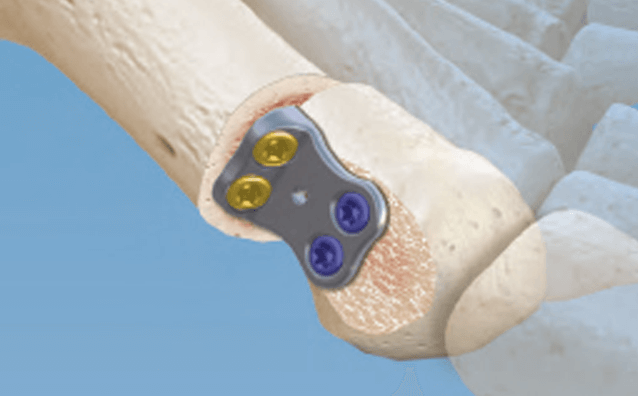

CONMED Foot and Ankle offers tailored innovation and simplified solutions. Explore our complete portfolio of arthroplasty, biologic, fixation, implant, suture anchor, and instrumentation offerings for foot and ankle surgery.

A Better Way to Do Surgery

Add value, increase efficiency, mitigate risk, and ensure UDI traceability. Our Smart Extremity Implant Management simplifies the sterilization sequence so you can focus on your procedures and patients.